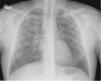

Description of CasesFive cases of MDR-TB were diagnosed. Their clinical characteristics are described in Table 4. It is interesting to observe that the delay in obtaining a microbiological diagnosis in the first case was 4 months, while for the last case, results were received within 72h. This improvement is associated with the introduction of polymerase chain reaction (PCR) techniques in respiratory samples in the reference hospital. In the index case, or case 1, the delay in diagnosis was confounded by an initial interpretation of community-acquired pneumonia (see chest X-ray in Fig. 1).